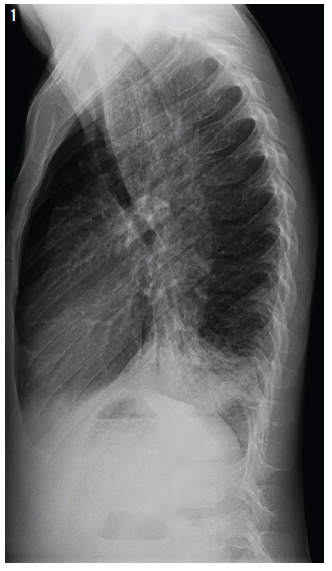

hodgkin's lymphoma

Melissa S. Singer, MD; Randi Sperling, DO; Vicki R. McGowan, II, DO

A 17-year-old girl presented to a community hospital with a several-month history of cough and congestion and a 3-week history of severe upper back pain that had resulted in her missing school.